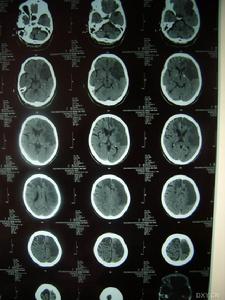

影像學檢查示:患者姐弟的CT均可見,但當地的CT顯示欠清楚。患者的頭顱CT可見多發白質變性;MRI清晰可見多發白質變性及小梗死病灶,病灶大小不一,均呈長T1、長T2信號,病灶累及雙側半球、腦室周圍、腦幹、橋腦,小腦未見病灶;梗死灶分布在底節區,MRA(血管的磁共振影像)顯示顱內血管正常。